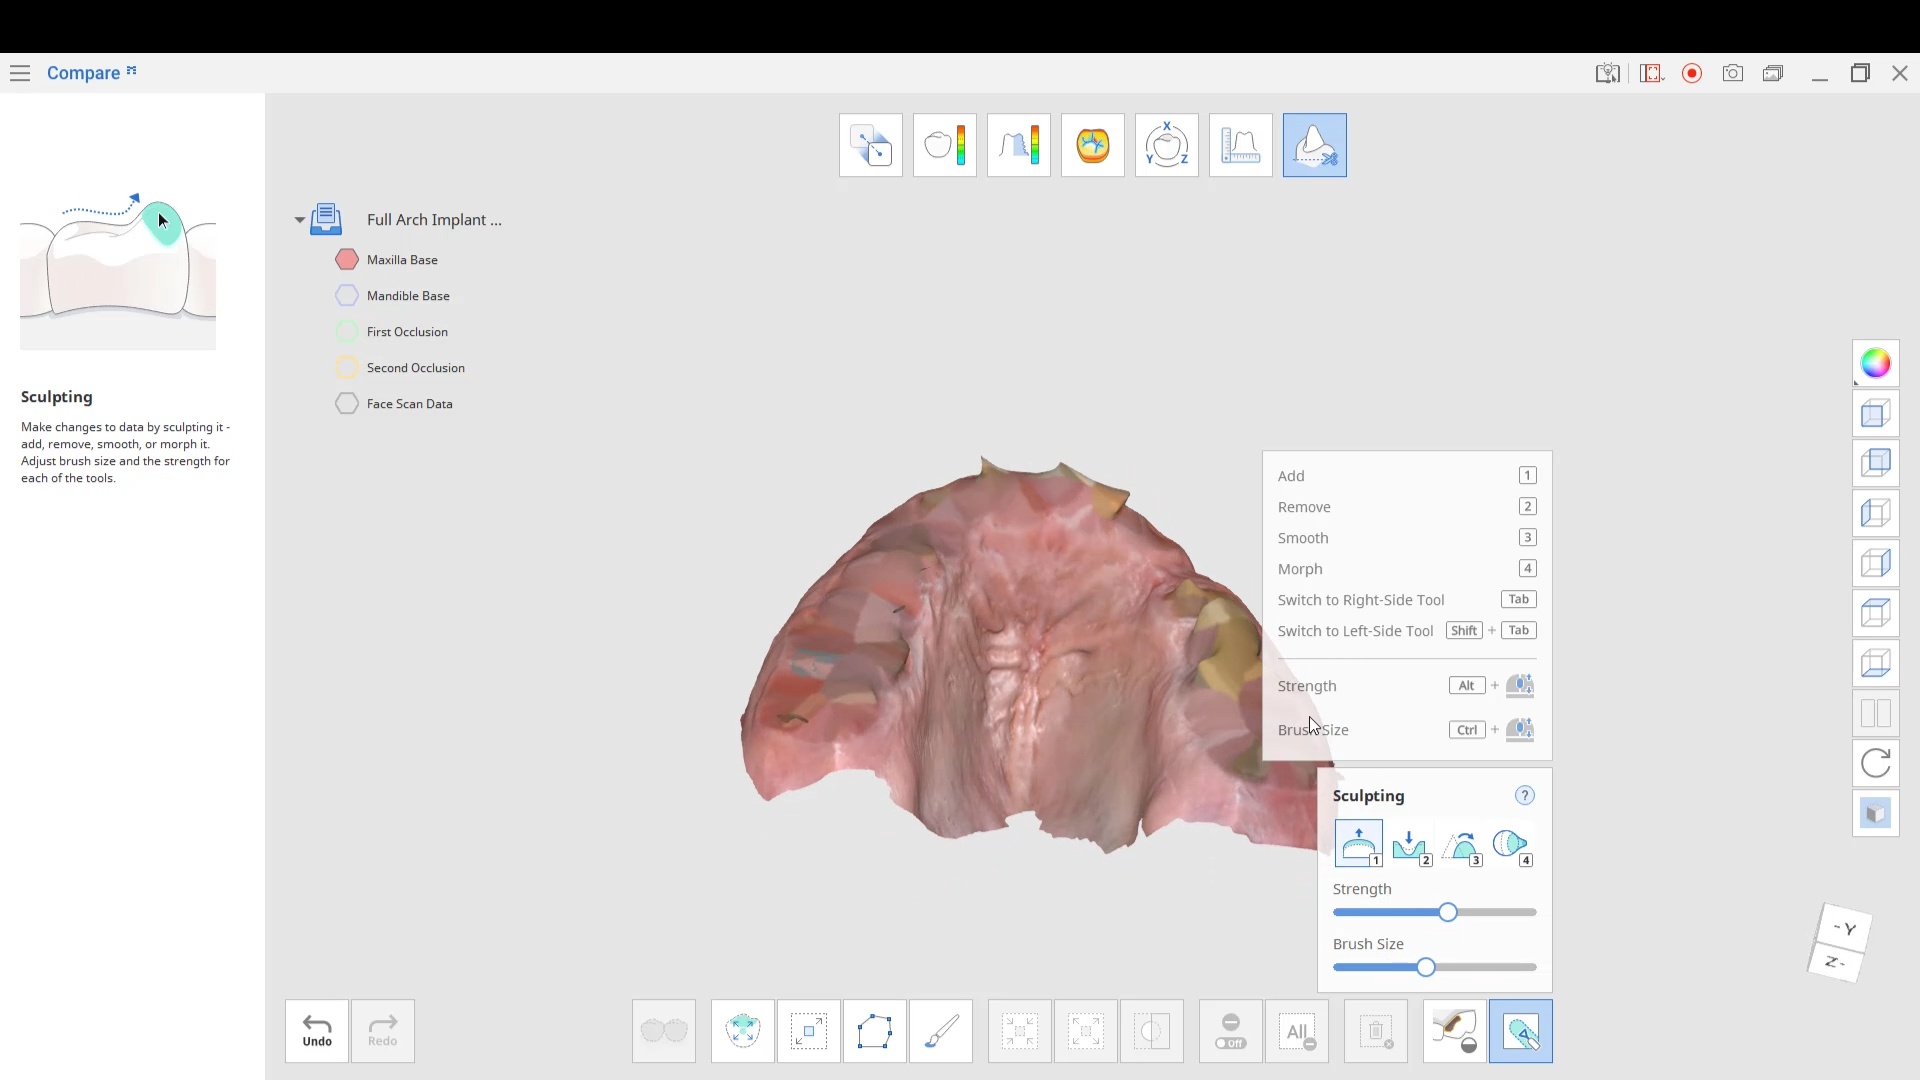

Full Arch Implant Planning Set Up with Medit i700

This used to be such a long process and we can bust them out in no time. take upper and lower scans in a minute. add lip…